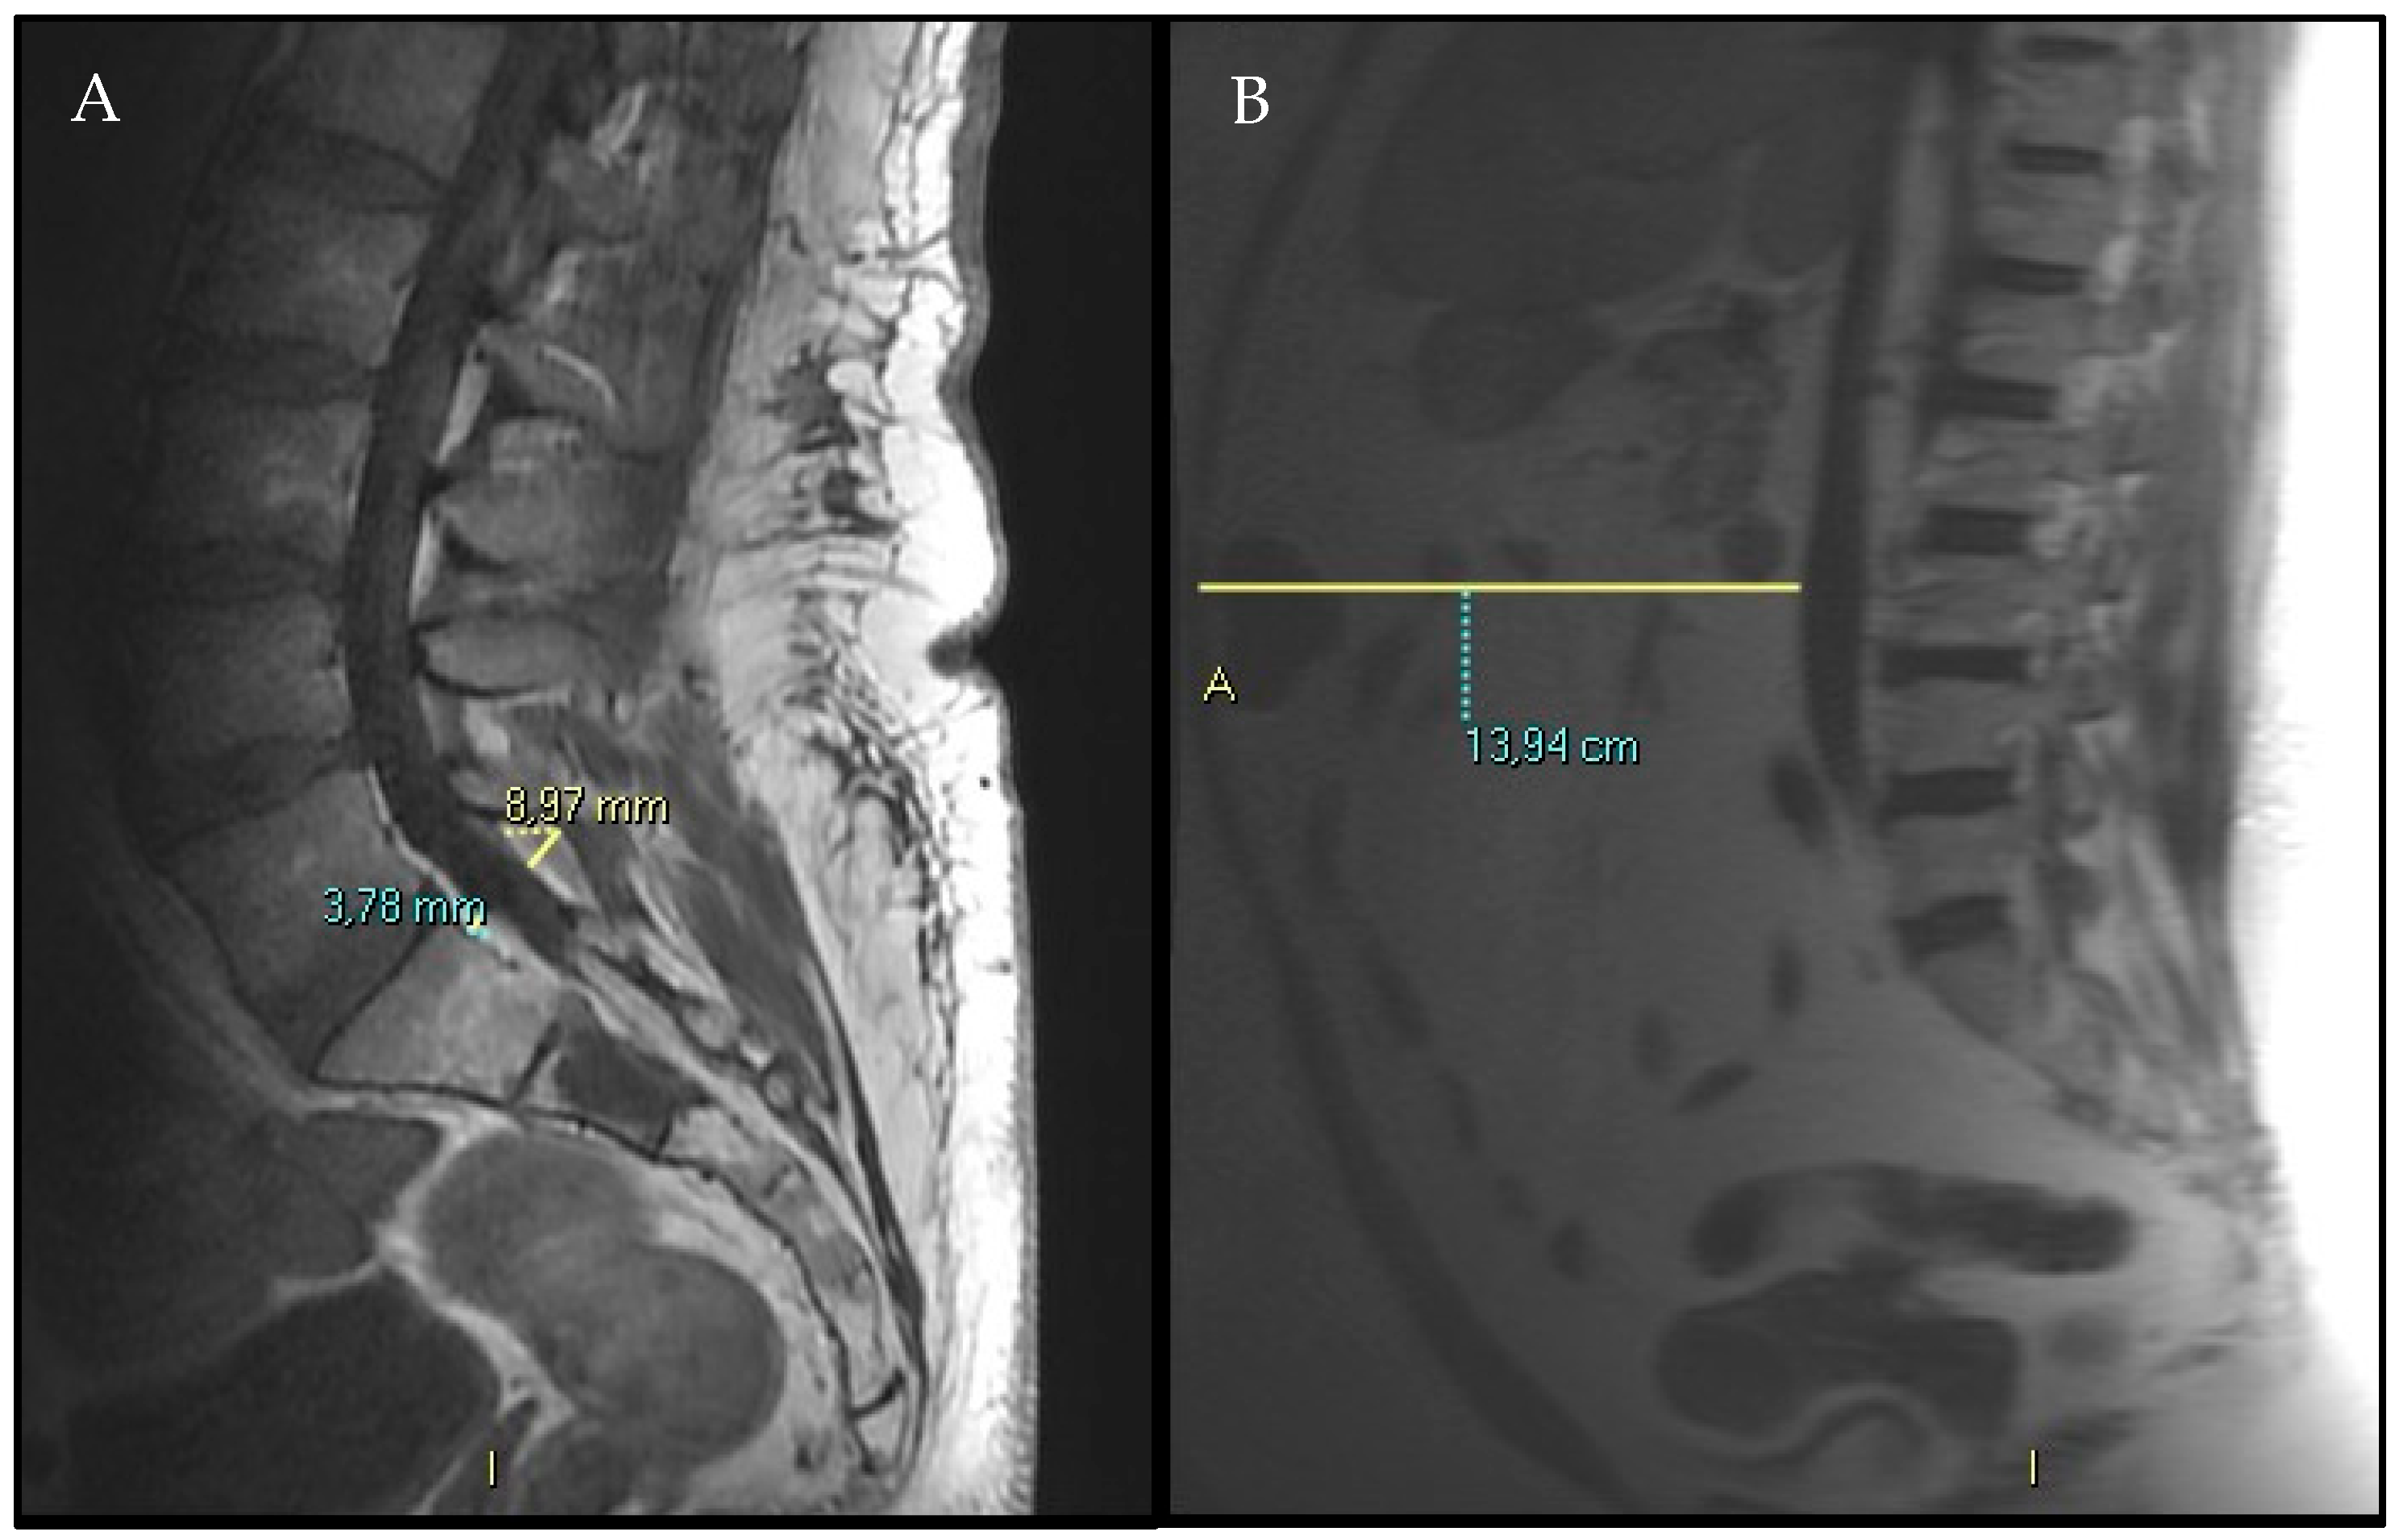

- Spinal canal antero-posterior diameter (SC), at the same level.